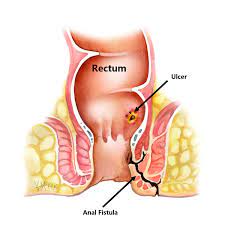

Overview

Package includes:

Days in hospital : 2 to 3 Days (For patient and one attendant)

Days in hotel : 7 Days (For patient and one attendant)

Room type in hospital : Shared

Room type in hotel : Private

Hotel category: Standard

Value added benefits of the Anal Fitsula:

Ø Doctor consultation charges

Ø Lab tests and diagnostic charges

Ø Room charges inside hospital during the procedure

Ø Surgeon Fee

Ø Nursing charges

Ø Hospital surgery suite charges

Ø Anesthesia charges

Ø Routine medicines and routine consumables (bandages, dressings etc.)

Ø Food and Beverages inside hospital stay for patient and one attendant.

Extra benefits:

ü Interpreter

ü Visa assistance

Ø Site tourism of the city

Ø Follow up with the doctor

Ø Airport pick up and drop

Ø Free online consultation with the doctor

Ø Priority appointments with the doctor

Ø Room upgrade from sharing to private